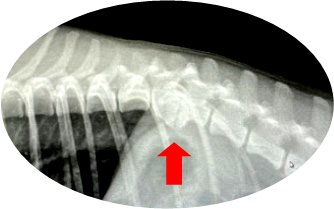

まずは下のレントゲン写真をご覧ください。

赤矢印の箇所の背骨(脊椎)が、他のところに比べて下に垂れ下がるように変形しているのがおわかりかと思います。これが「変形性脊椎症」です。同様に「変形性関節症」も、膝の関節や肘や手首の関節が変形する病気です。変形した軟骨が炎症を引き起こし、ひどい痛みをおこします。しかし「ひどい痛みがある」とは言っても、わんちゃんやネコちゃんは痛みを口にすることはできませんし、痛みがあってもなかなか症状を見せてくれません。